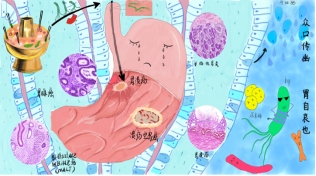

作品名称:《众口传幽,胃自哀也》

作者:马文宇

指导老师:王成勤

作品简介:众所周知,中国传统饮食习惯中很少分餐,聚会时也很少使用公筷,大大增加了幽门螺旋杆菌传播的风险,增加了许多患肠胃相关疾病潜在的可能性。本作品以大多数国人聚餐时幽门螺旋杆菌的口-口传播为切入点,重点描述了幽门螺旋杆菌可能对消化系统造成的疾病:萎缩性胃炎、胃溃疡、胃腺癌及黏膜相关组织淋巴瘤四种疾病。希望可以通过本作品让人们认识到幽门螺旋杆菌的可怕,呼吁人们进行分餐制、聚餐时使用公筷,养成良好的生活习惯,免受幽门螺旋杆菌之痛!